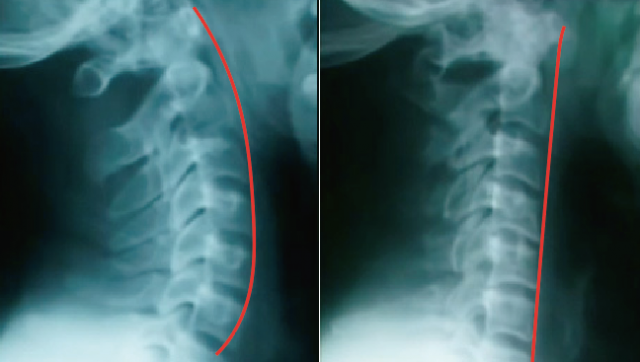

・ストレートネックになっている

頭痛の起こる人のほとんどに頚椎の歪み、左右の可動域の差、頭の傾き、関節のロック(ひっかかり)があり、そこに仕事での負担や生活リズムの乱れ、食事の偏りからの貧血や低血糖が重なっていいるところに気圧の変化で低気圧が近づいてくると血管が拡張され三叉神経が刺激され頭痛は一気にきつくなります。

歪みを簡単にチェックするには、左右の首の動きやバンザーイしたときの手の長さ、自分の指で首を抑えるとゴリゴリと痛い感じがある方は歪みやストレートネックになっていることが多いのでまずは歪みを調整することが大切です。